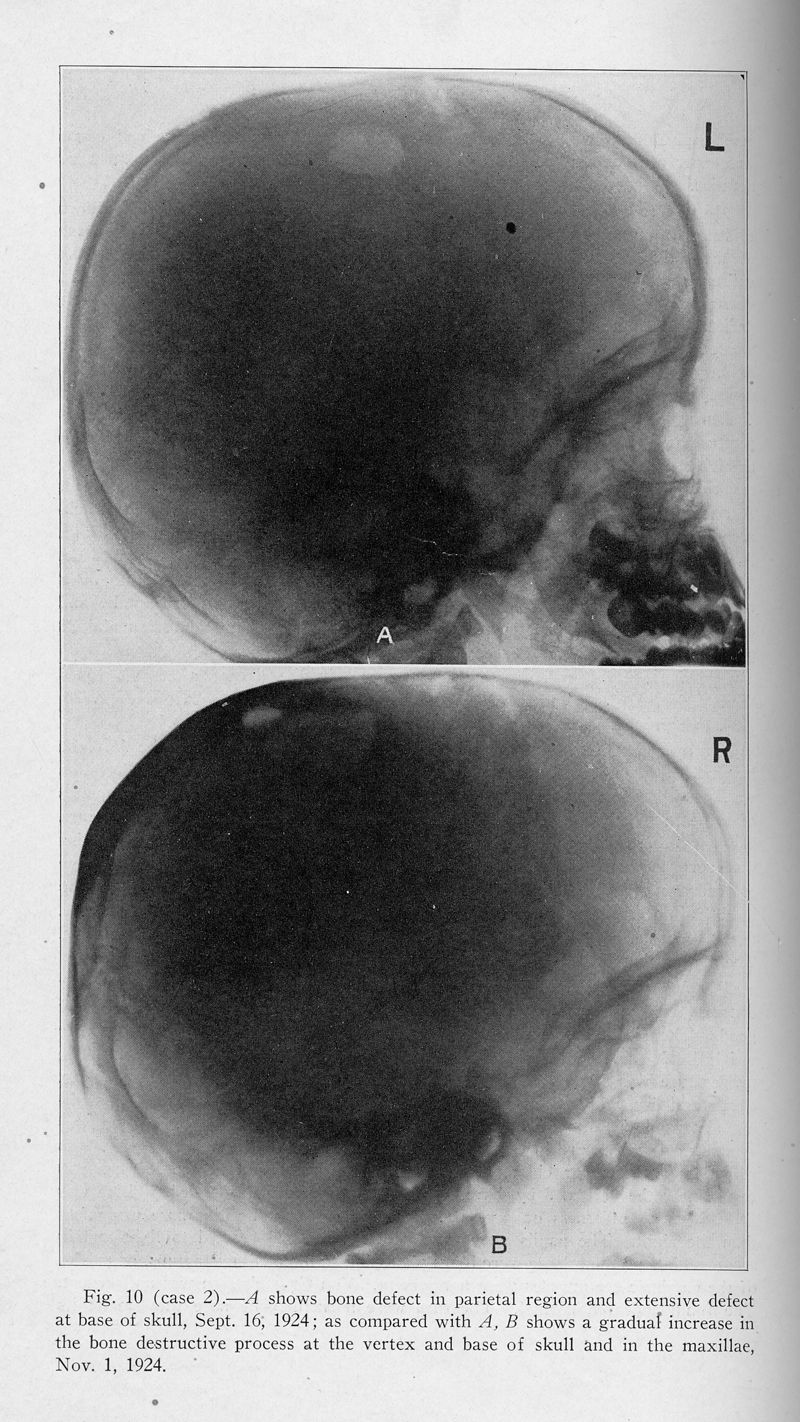

Xanthomatosis and the reticuloendothelial system. Correlation of an unidentified group of cases described as defects in membranous bones, exophthalmos and diabetes insipidus (Christian's syndrome)

In : Archives of internal medicine (1908), 1928, Vol. 42, pp. 611-74